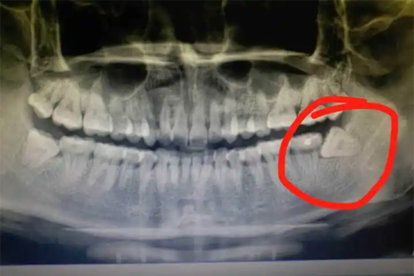

傾斜生長(zhǎng)的智齒會(huì)持續(xù)擠壓鄰牙牙根,導(dǎo)致前牙擁擠移位或牙根吸收。正畸治療后的患者可能出現(xiàn)牙齒復(fù)發(fā)畸形,需通過曲面斷層片評(píng)估后拔除阻生齒。鄰牙已出現(xiàn)明顯移位時(shí),可能需聯(lián)合正畸治療恢復(fù)咬合關(guān)系。

長(zhǎng)期存在的阻生智齒可能刺激頜骨形成含牙囊腫或角化囊腫,X線可見透射影伴骨質(zhì)破壞。囊腫增大可導(dǎo)致病理性骨折或神經(jīng)壓迫,需手術(shù)摘除囊腫并拔除患牙。術(shù)后需定期復(fù)查排除復(fù)發(fā)可能。